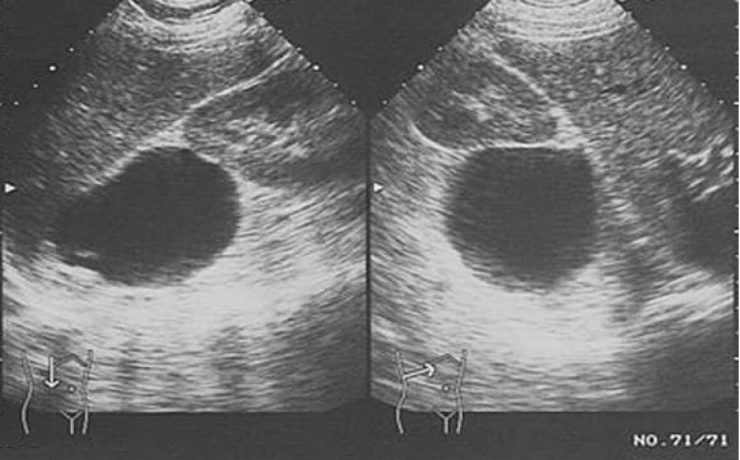

Más del 95% de las enfermedades biliares, son debidas a colelitiasis. En Estados Unidos su costo anual asciende a 8 millones de dólares, el 40% de los mayores de 40 años tiene colelitiasis y10 a 30% presentaran síntomas. 11% de la población adulta de E.U.A. Tiene cálculos biliares y esta